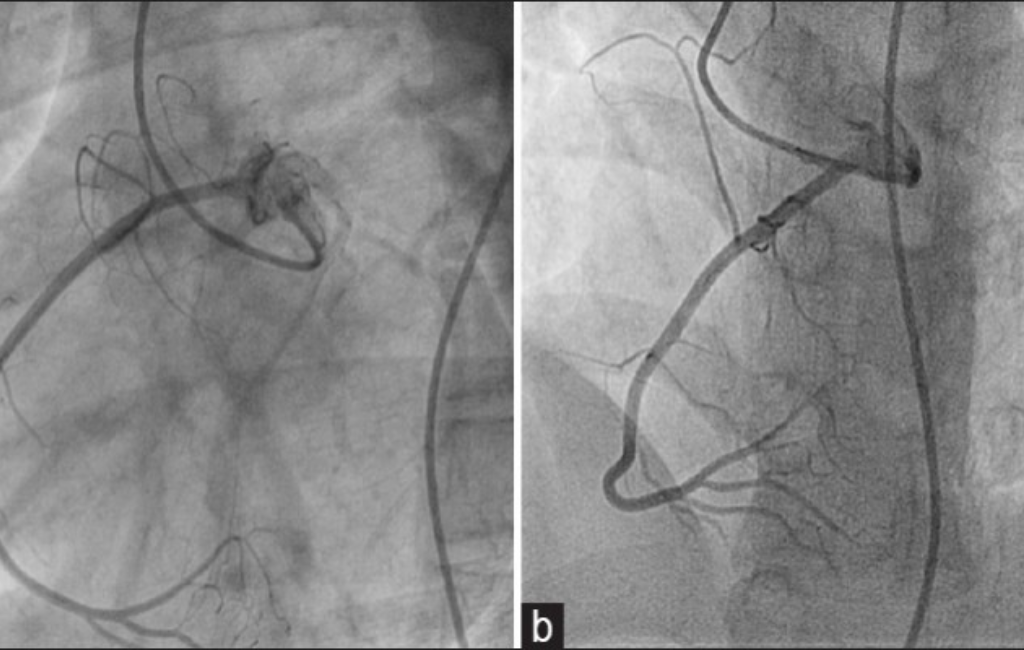

Angioplasty & Stent Placement – Restoring Blood Flow to the Heart

• Balloon Angioplasty & Stenting – Non-surgical, quick recovery treatment for heart blockages.

• Drug-Eluting & Bioabsorbable Stents – Advanced solutions for artery widening.

Before & After

Cardic Surgery Results